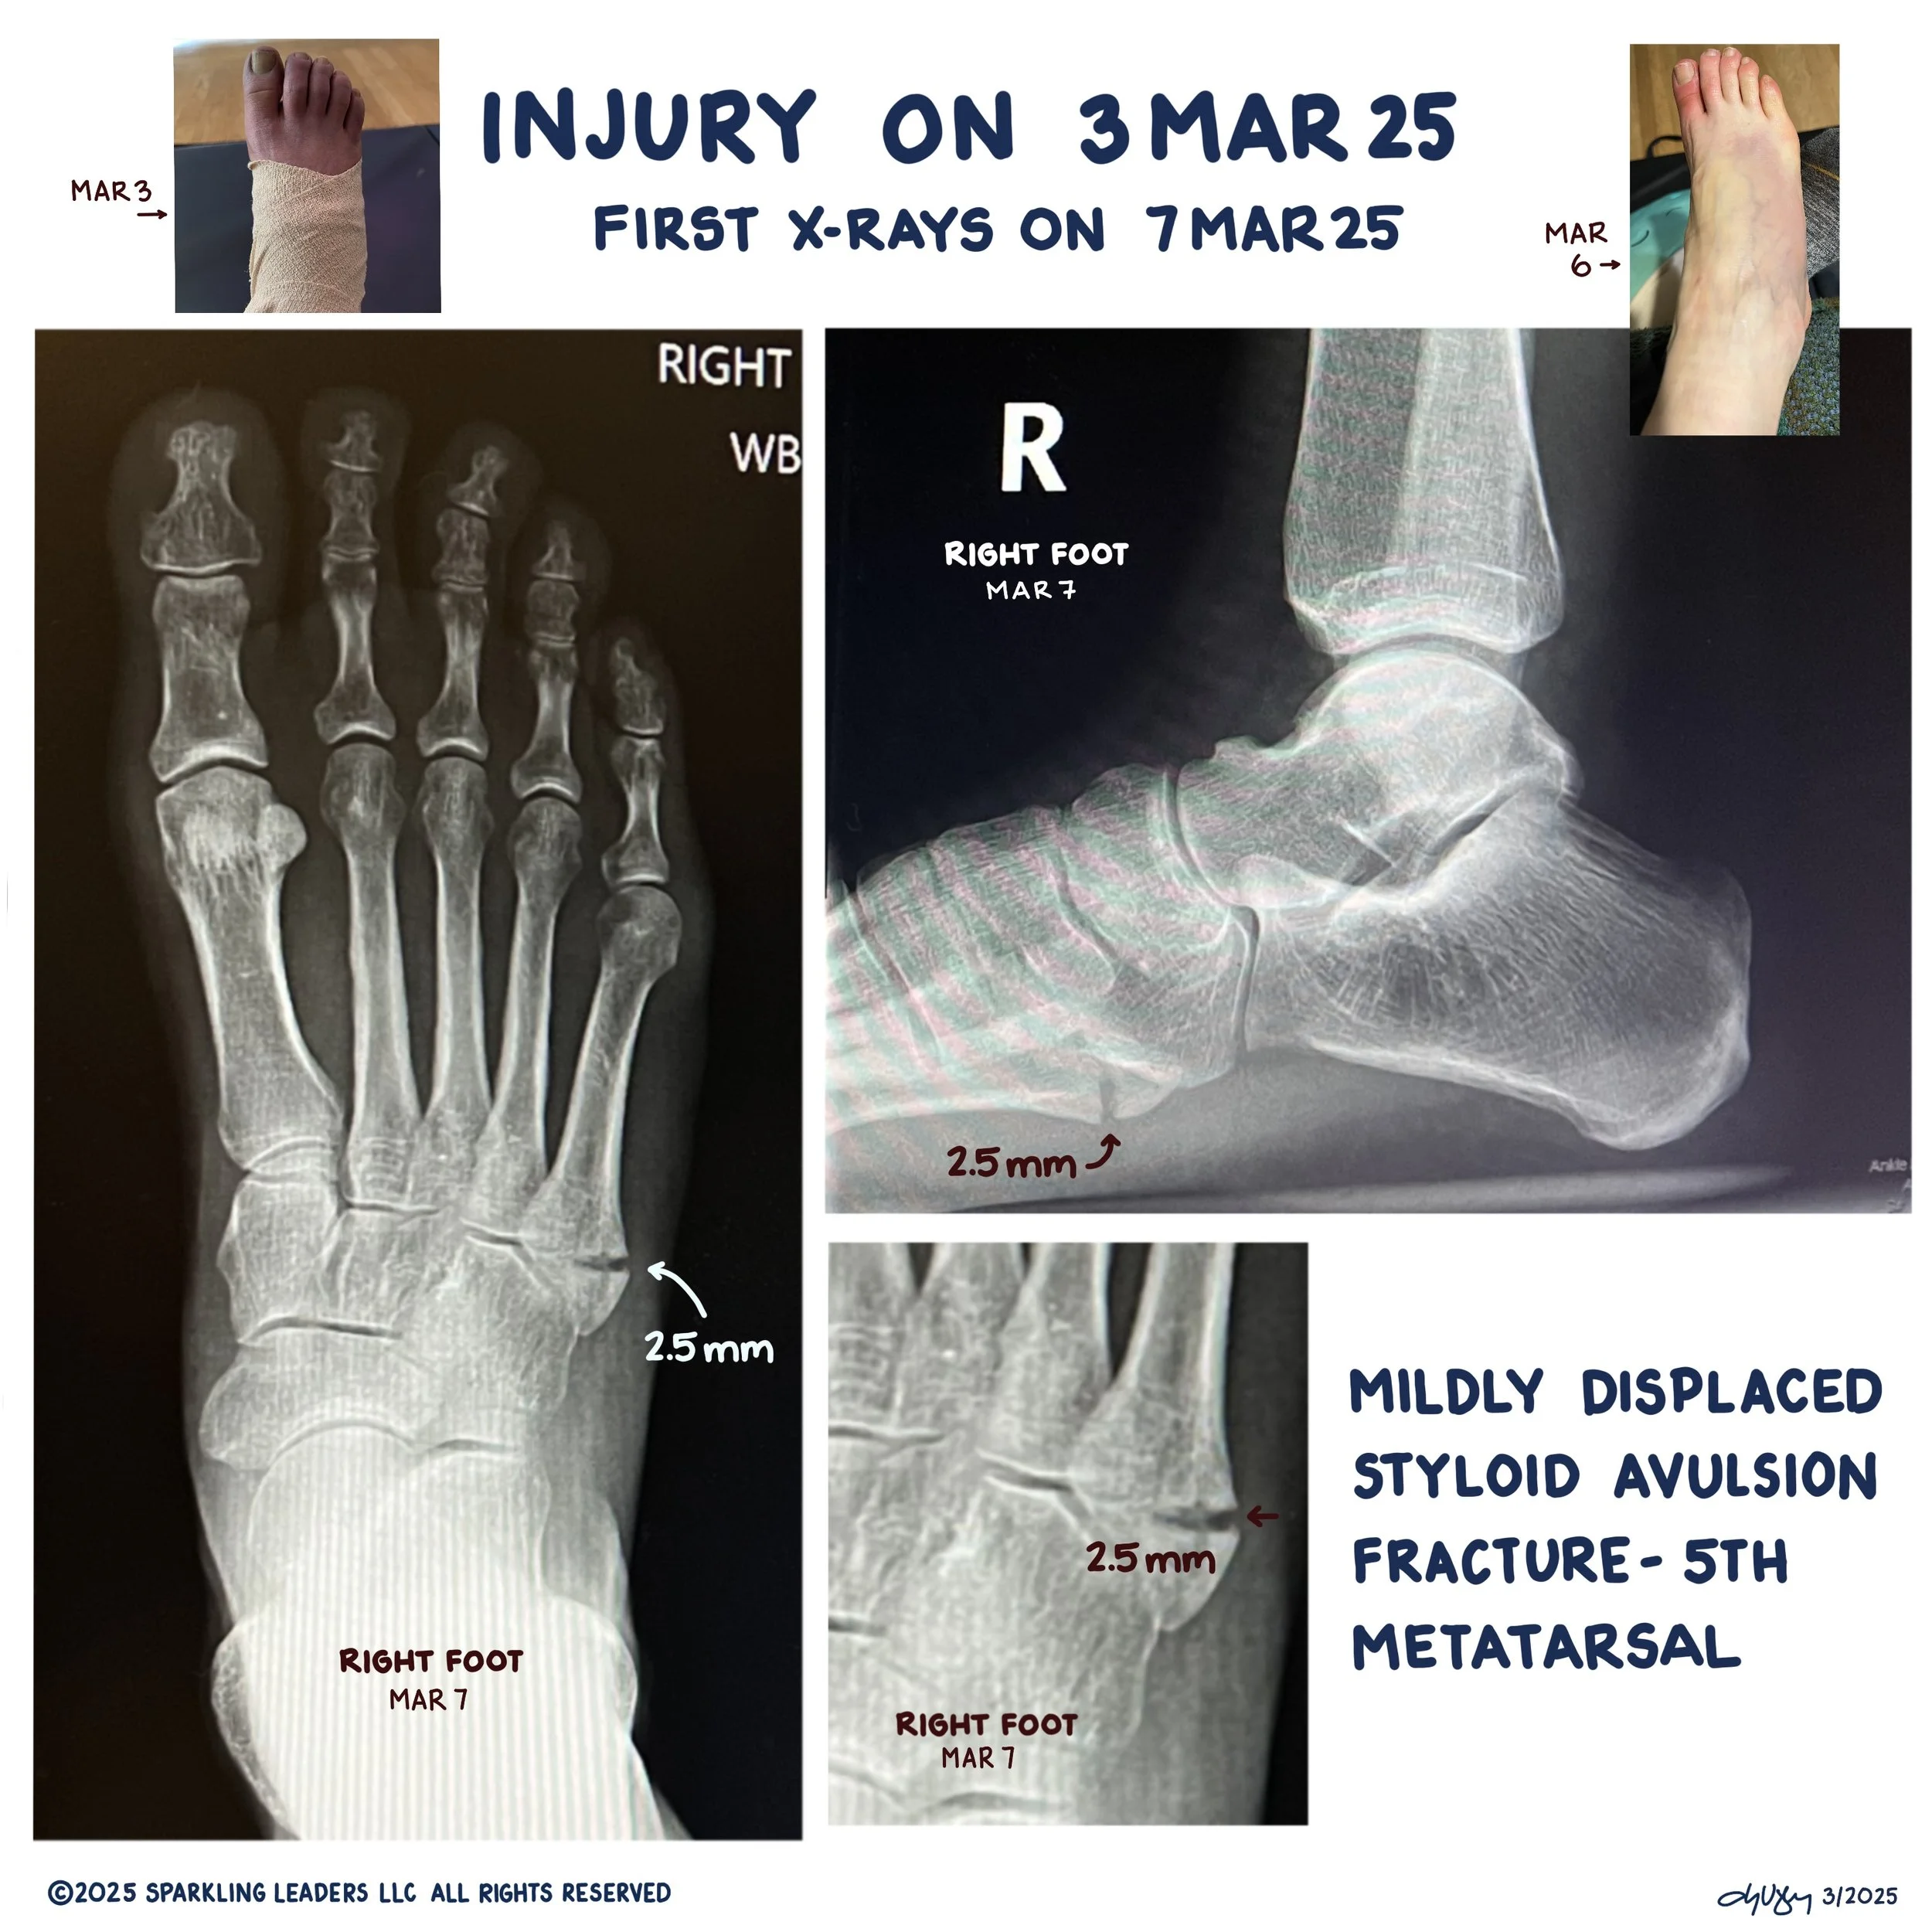

I broke my fifth metatarsal on Mar 3 around 8:30 am. Below is my journey in hopes it can help others.

Mar 3 (Day 1) - indoor bike workout wishing it wasn’t a day off and I could run. Not sure why that was going through my mind. Decided to finally donate the kids’ soccer balls and was carrying them to the car (two large bags with 10+ each) in my Oofoo slides when I tripped over a plastic gutter drain with my left foot and landed off balance on it with my right. I felt my foot roll off the slide as the plastic piece tilted and I rolled off of it. The pain was intense but the worst part was the fear that it was similar to when I tore my ACL off the bone in college (first year, second day of ski team practice).

Mar 7 (Day 5) - 31 minute indoor bike and then my PT could see me. She didn’t love how it was presenting and told me I needed x-rays. She prepared me for what they might say. I was able to get in to see a doctor and was told I had broken my fifth metatarsal and to wear a post op shoe or boot. It would take about 4 to 6 weeks to heal. I asked about running and the doctor put in an urgent request for me to see a podiatric surgeon. Steps: 5955

Apr 29 (Day 58) So nervous about getting the x-rays and also feeling stronger. Doing more. Didn’t take crutches in to the appointment and then had to stand for the x-rays. And… the x-rays didn’t show enough bone growth so 4 more weeks in the boot. Full-time, still sleeping in it. So sad. Also saw another fracture we couldn’t see in the original x-rays that has some bone growth. Vacillating between wallowing and looking for opportunity. Steps: 5335